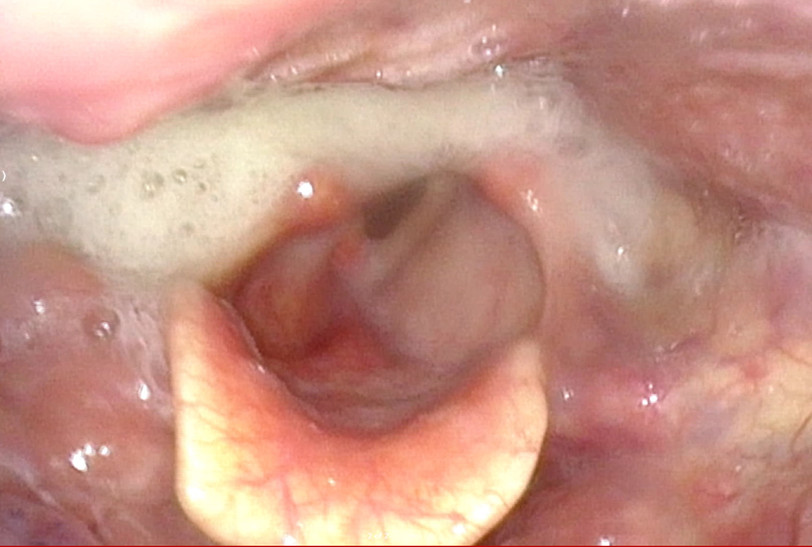

FEES: Residue in the hypopharynx; penetrations.

Proposed surgery: Pharyngoplasty and cricopharyngeal myotomy.